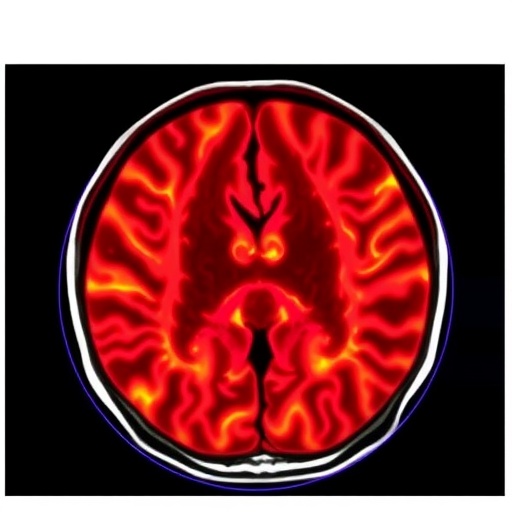

The pancreas, a vital yet elusive organ, has long posed diagnostic challenges due to the subtle nature and varied morphology of its solid neoplasms. Conventional imaging interpretation often requires expert radiologists and can involve subjective variability. The novel approach developed leverages a three-dimensional neural network architecture known as nnU-Net, which excels in medical image segmentation by learning from volumetric MRI data, allowing for precise delineation of tumor boundaries with minimal human intervention.

The study retrospectively analyzed MRI scans from patients who had undergone surgical resection for pancreatic tumors. The training dataset included 165 patients, while 89 were reserved for testing the generalizability of the model. The MRI sequences principally consisted of T2-weighted imaging (T2WI) and diffusion-weighted imaging (DWI), modalities that provide complementary tissue contrast necessary for differentiating neoplastic tissue from normal pancreatic parenchyma.

Performance evaluation of the deep learning segmentation model revealed impressive quantitative metrics, with a mean Dice Similarity Coefficient (DSC) reaching 0.82 on T2WI and an astonishing 0.91 on DWI within the training cohort. These high DSC values indicate a near-expert level of overlap between the algorithm’s predicted segmentations and manually annotated ground truths. Despite a natural performance dip in the independent testing cohort, DSCs of 0.64 on T2WI and 0.70 on DWI still underscored significant segmentation reliability.